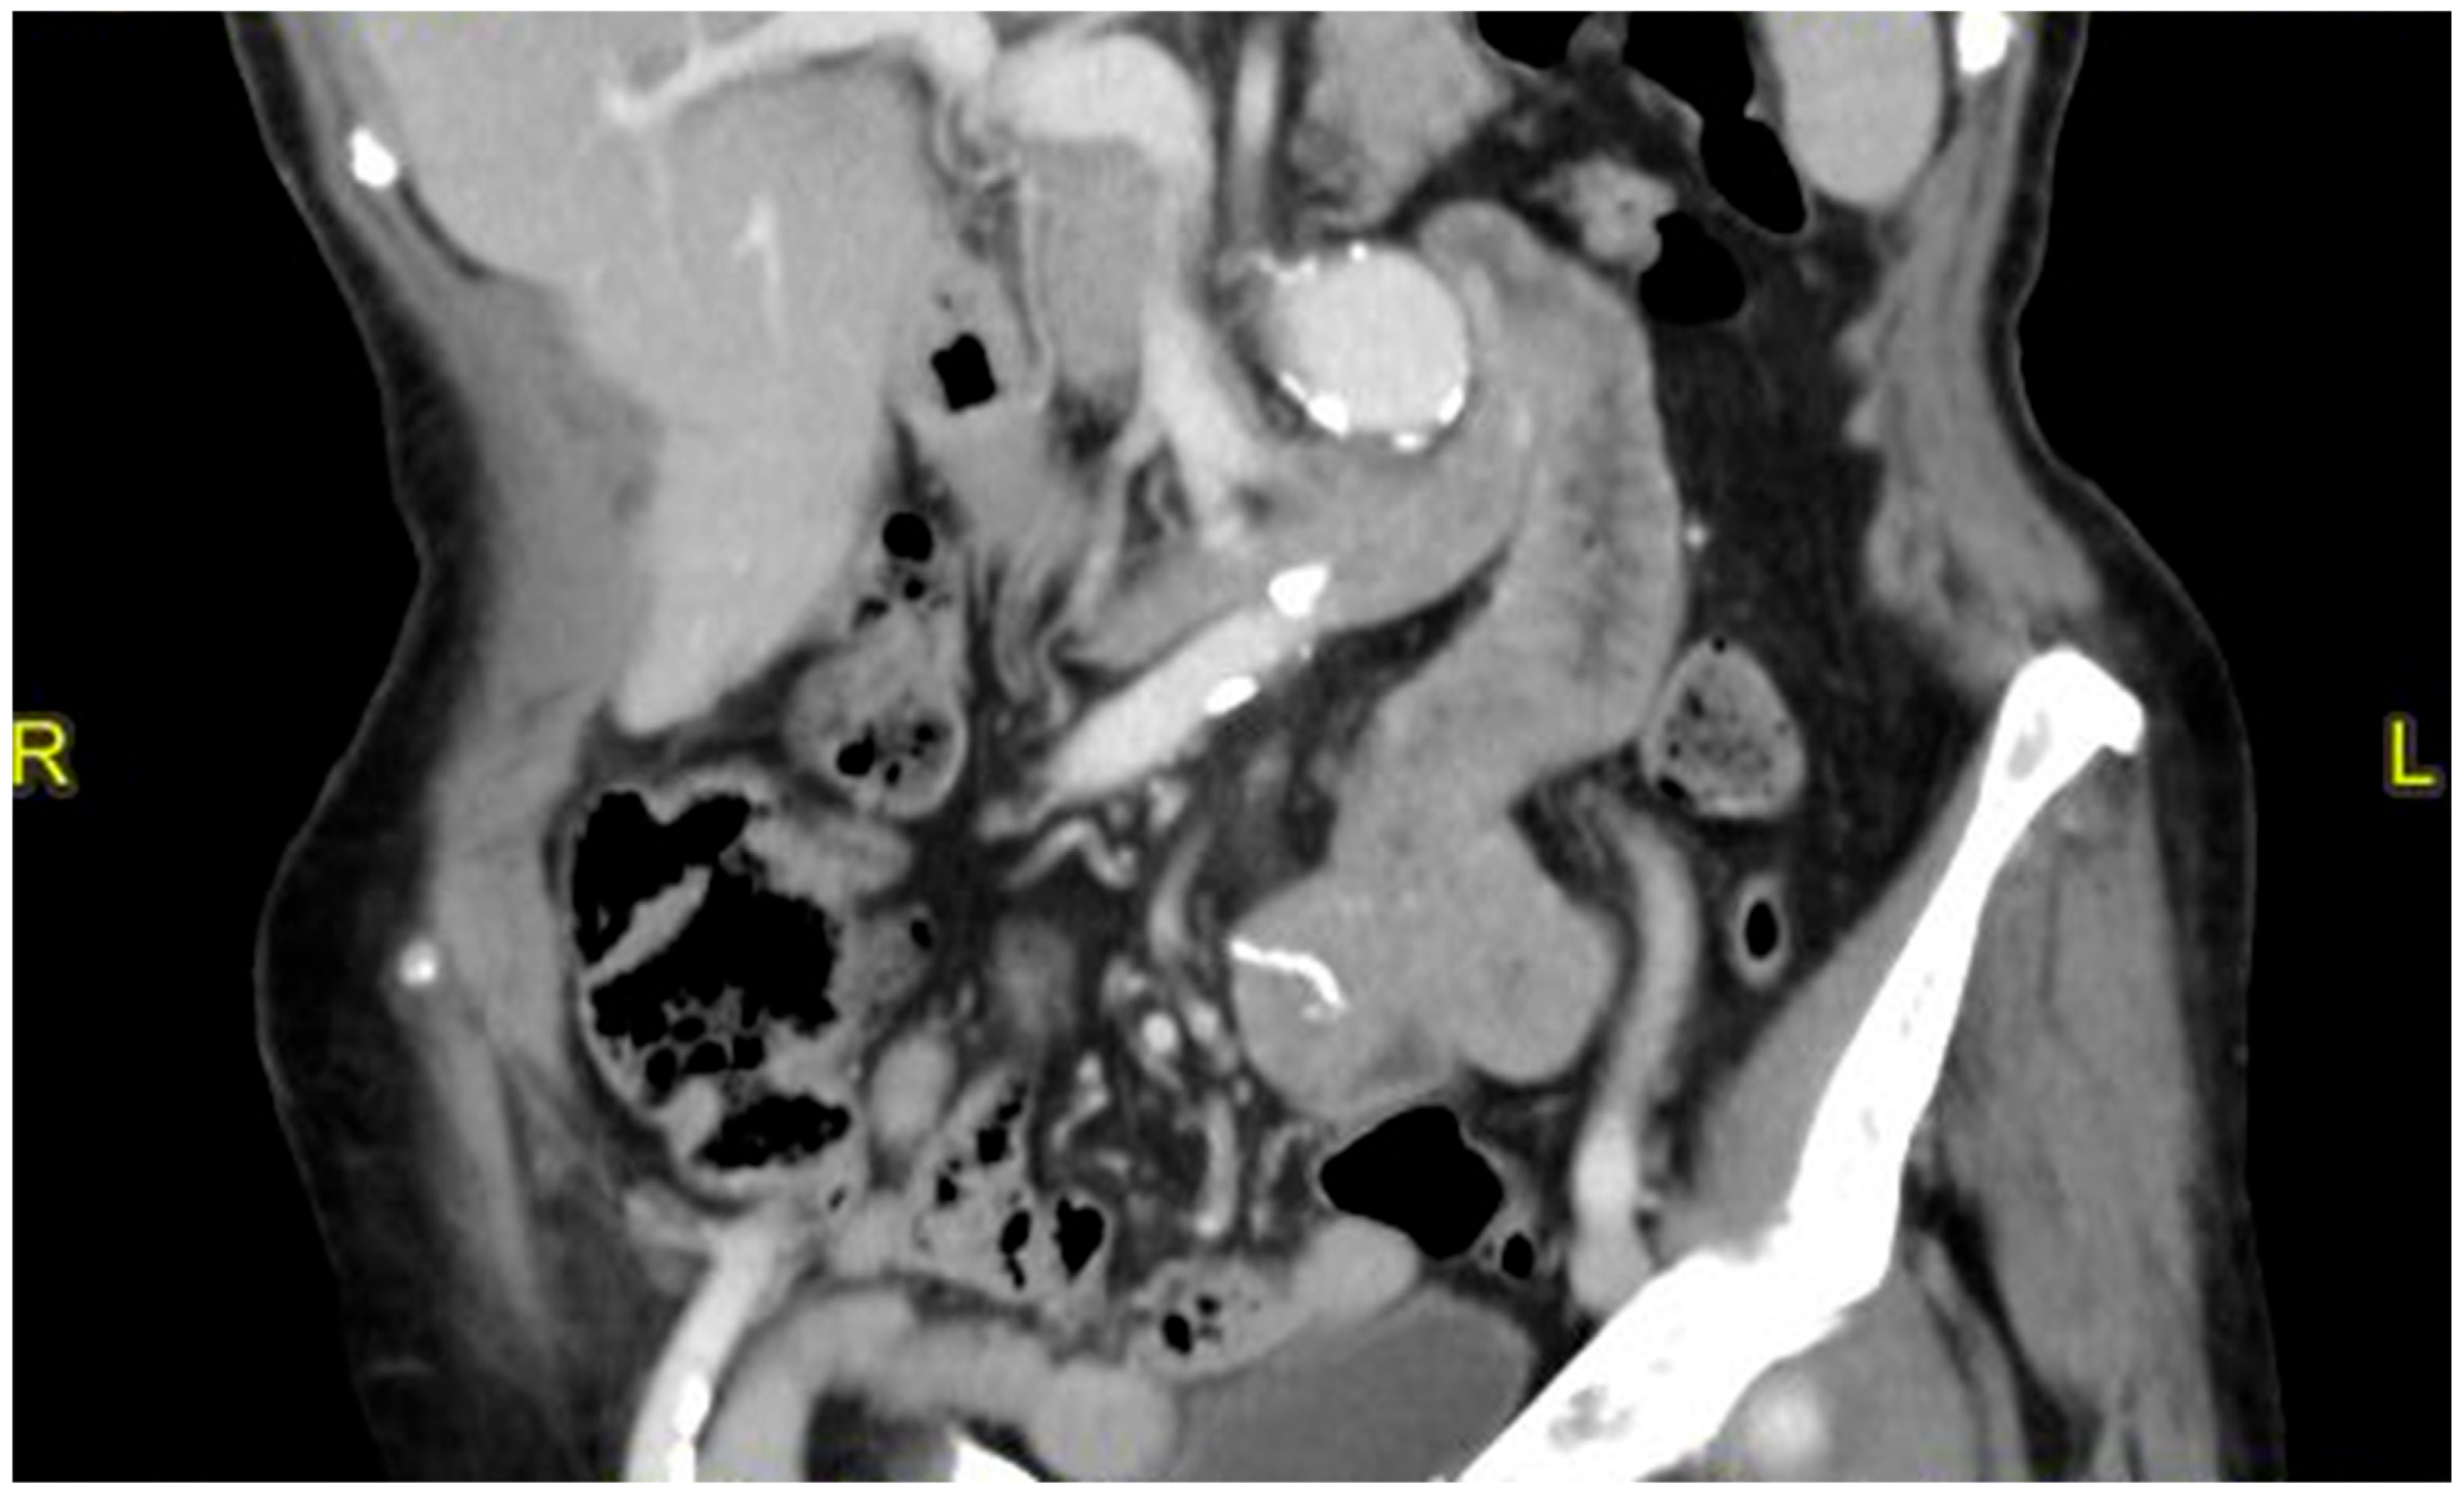

2. Case Presentation